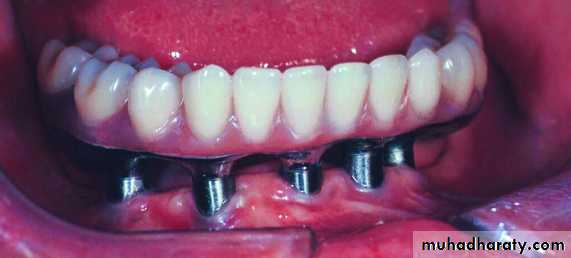

Two-Implant Bar Overdenture

Clinical photograph showing abutments immediatelyafter removal of sutures

Implants joined by over denture bar over whichprosthetic restoration is to be placed

Clips in denture which snap onto bar for retentionand support of denture

Clinical photograph showing prosthetic restorationadapted to implants